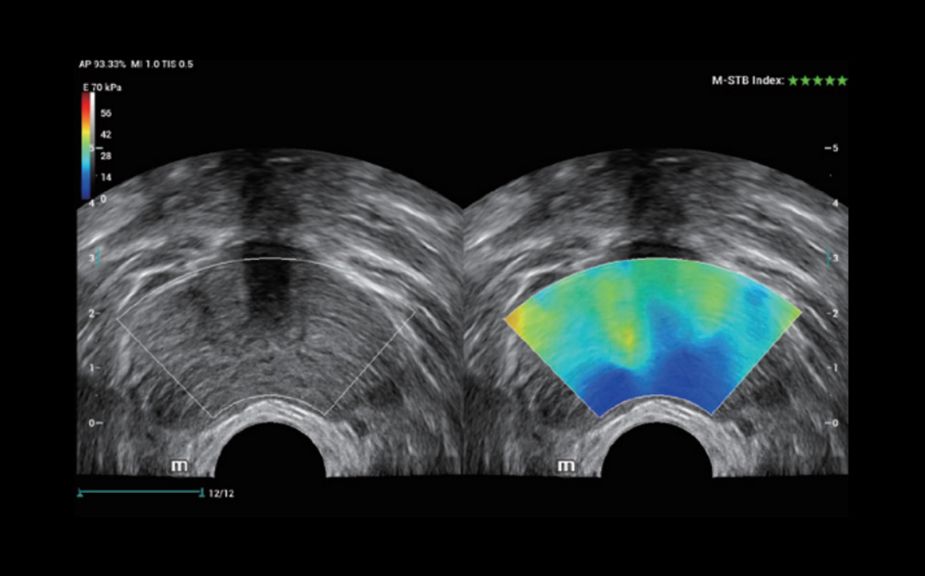

Innowacyjna Elastografia: HiFR STE

Do 10 razy szybsza cz?stotliwo?? od?wie?ania obrazu elastografii STE

Bardziej czu?e wykrywanie ruchu dla lepszej stabilno?ci i wi?kszej dok?adno?ci

HiFR STE ŌĆō nowotw├│r piesi

HiFR STE - w?troba

Innowacyjna Elastografia: HiFR STE

Do 10 razy szybsza cz?stotliwo?? od?wie?ania obrazu elastografii STE

Bardziej czu?e wykrywanie ruchu dla lepszej stabilno?ci i wi?kszej dok?adno?ci

HiFR STE ŌĆō nowotw├│r piesi

HiFR STE - w?troba